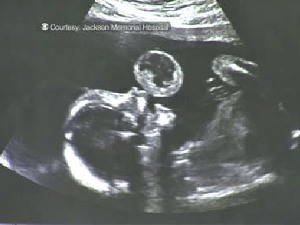

Surgery in Utero Removes Tumor

I came across a story on Live Action News this morning and had to share. . . The first successful surgery on an unborn child in the womb to remove tumor was recently performed. The surgery was a success and the baby was born with nothing but a little scar on her lip. (read the story at Live Action News).

It is so beautiful to see all that can be accomplished within the mother’s womb from how quickly the child develops to how a successful surgery can be performed on a child when a tumor is detected. Yet, simultaneously the unborn children’s value is not always upheld and such efforts are not taken to protect their lives.